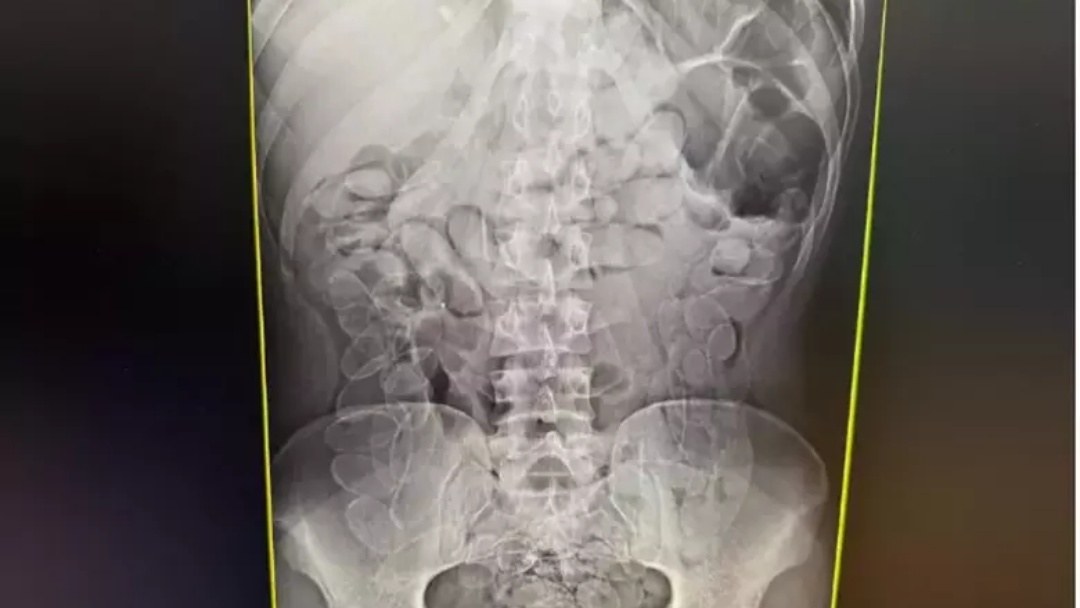

Ainda segundo o boletim de ocorrência, a mulher afirmou ter ingerido as cápsulas em território boliviano há cerca de sete dias e que permaneceu com o material no organismo durante todo esse período. Um exame de raio X da região abdominal revelou múltiplos invólucros no estômago.